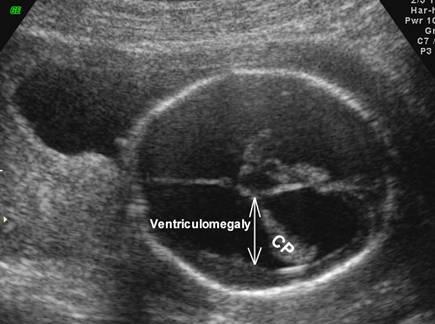

What is the function of the choroid plexus?

produce cerebrospinal fluid

Choroid Plexus

What is the size of the choroid plexus at 20 week scan?

10 mm or less

Why is the choroid plexus image taken?

to exclude ventricular megaly

What is a dangling choroid plexus caused by?

ventricular megaly

dangling choroid plexus